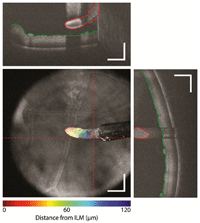

Figura 2).

Figura 2. Imágenes de OCT con tecnología swept-source. (A) DRI-OCT-1 Atlantis (Topcon, Japón). Paciente con coriorretinopatía serosa central. Debido a la mayor velocidad de escaneo del aparato, el número de scans en modo A obtenidos en una única captura es mucho mayor, permitiendo una vez procesados obtener una imagen de alta calidad. Del mismo modo, debido a la mayor penetración del laser de 1050 nm se aprecian detalles del límite de la coroides externa, cubriendo un área de escaneo más grande, de hasta 12 mm, incluyendo el área de la cabeza del nervio óptico y la retina temporal a la fóvea en una única imagen. (Fuente: http://www.topcon.co.jp/en/eyecare/product/diag/oct/dri_oct-1.html) (B) CASIA OCT SS-1000 (Tomey, Japón). La tecnología swept-source permite obtener imágenes tridimensionales del segmento anterior en una única captura con una resolución axial de 10 micras y una resolución transversal de 30 micras. (Fuente: http://www.tomey.com/Products/OCT/SS-1000CASIA.html).

Estos dispositivos

swept-source tienen el potencial de aumentar todavía más la velocidad de adquisición de imágenes. El dispositivo DRI-OCT-1 tiene una velocidad de adquisición de imágenes de 100.000

scans en modo A por segundo. Dado que la motilidad ocular limita el tiempo de adquisición de imágenes en la práctica clínica habitual, esta mejoría en el tiempo de captura posibilita el escaneado de áreas mucho mayores de tejido (por ejemplo 12 x 9 mm en el caso del DRI-OCT en comparación con 6 x 6 mm con el 3D OCT o el Cirrus OCT) e incluso una reconstrucción tridimensional completa del polo posterior. Existen prototipos en fase de investigación con velocidades de captura de imágenes aún mayores. Por ejemplo, se han descrito velocidades de adquisición de imágenes de 6.700.000